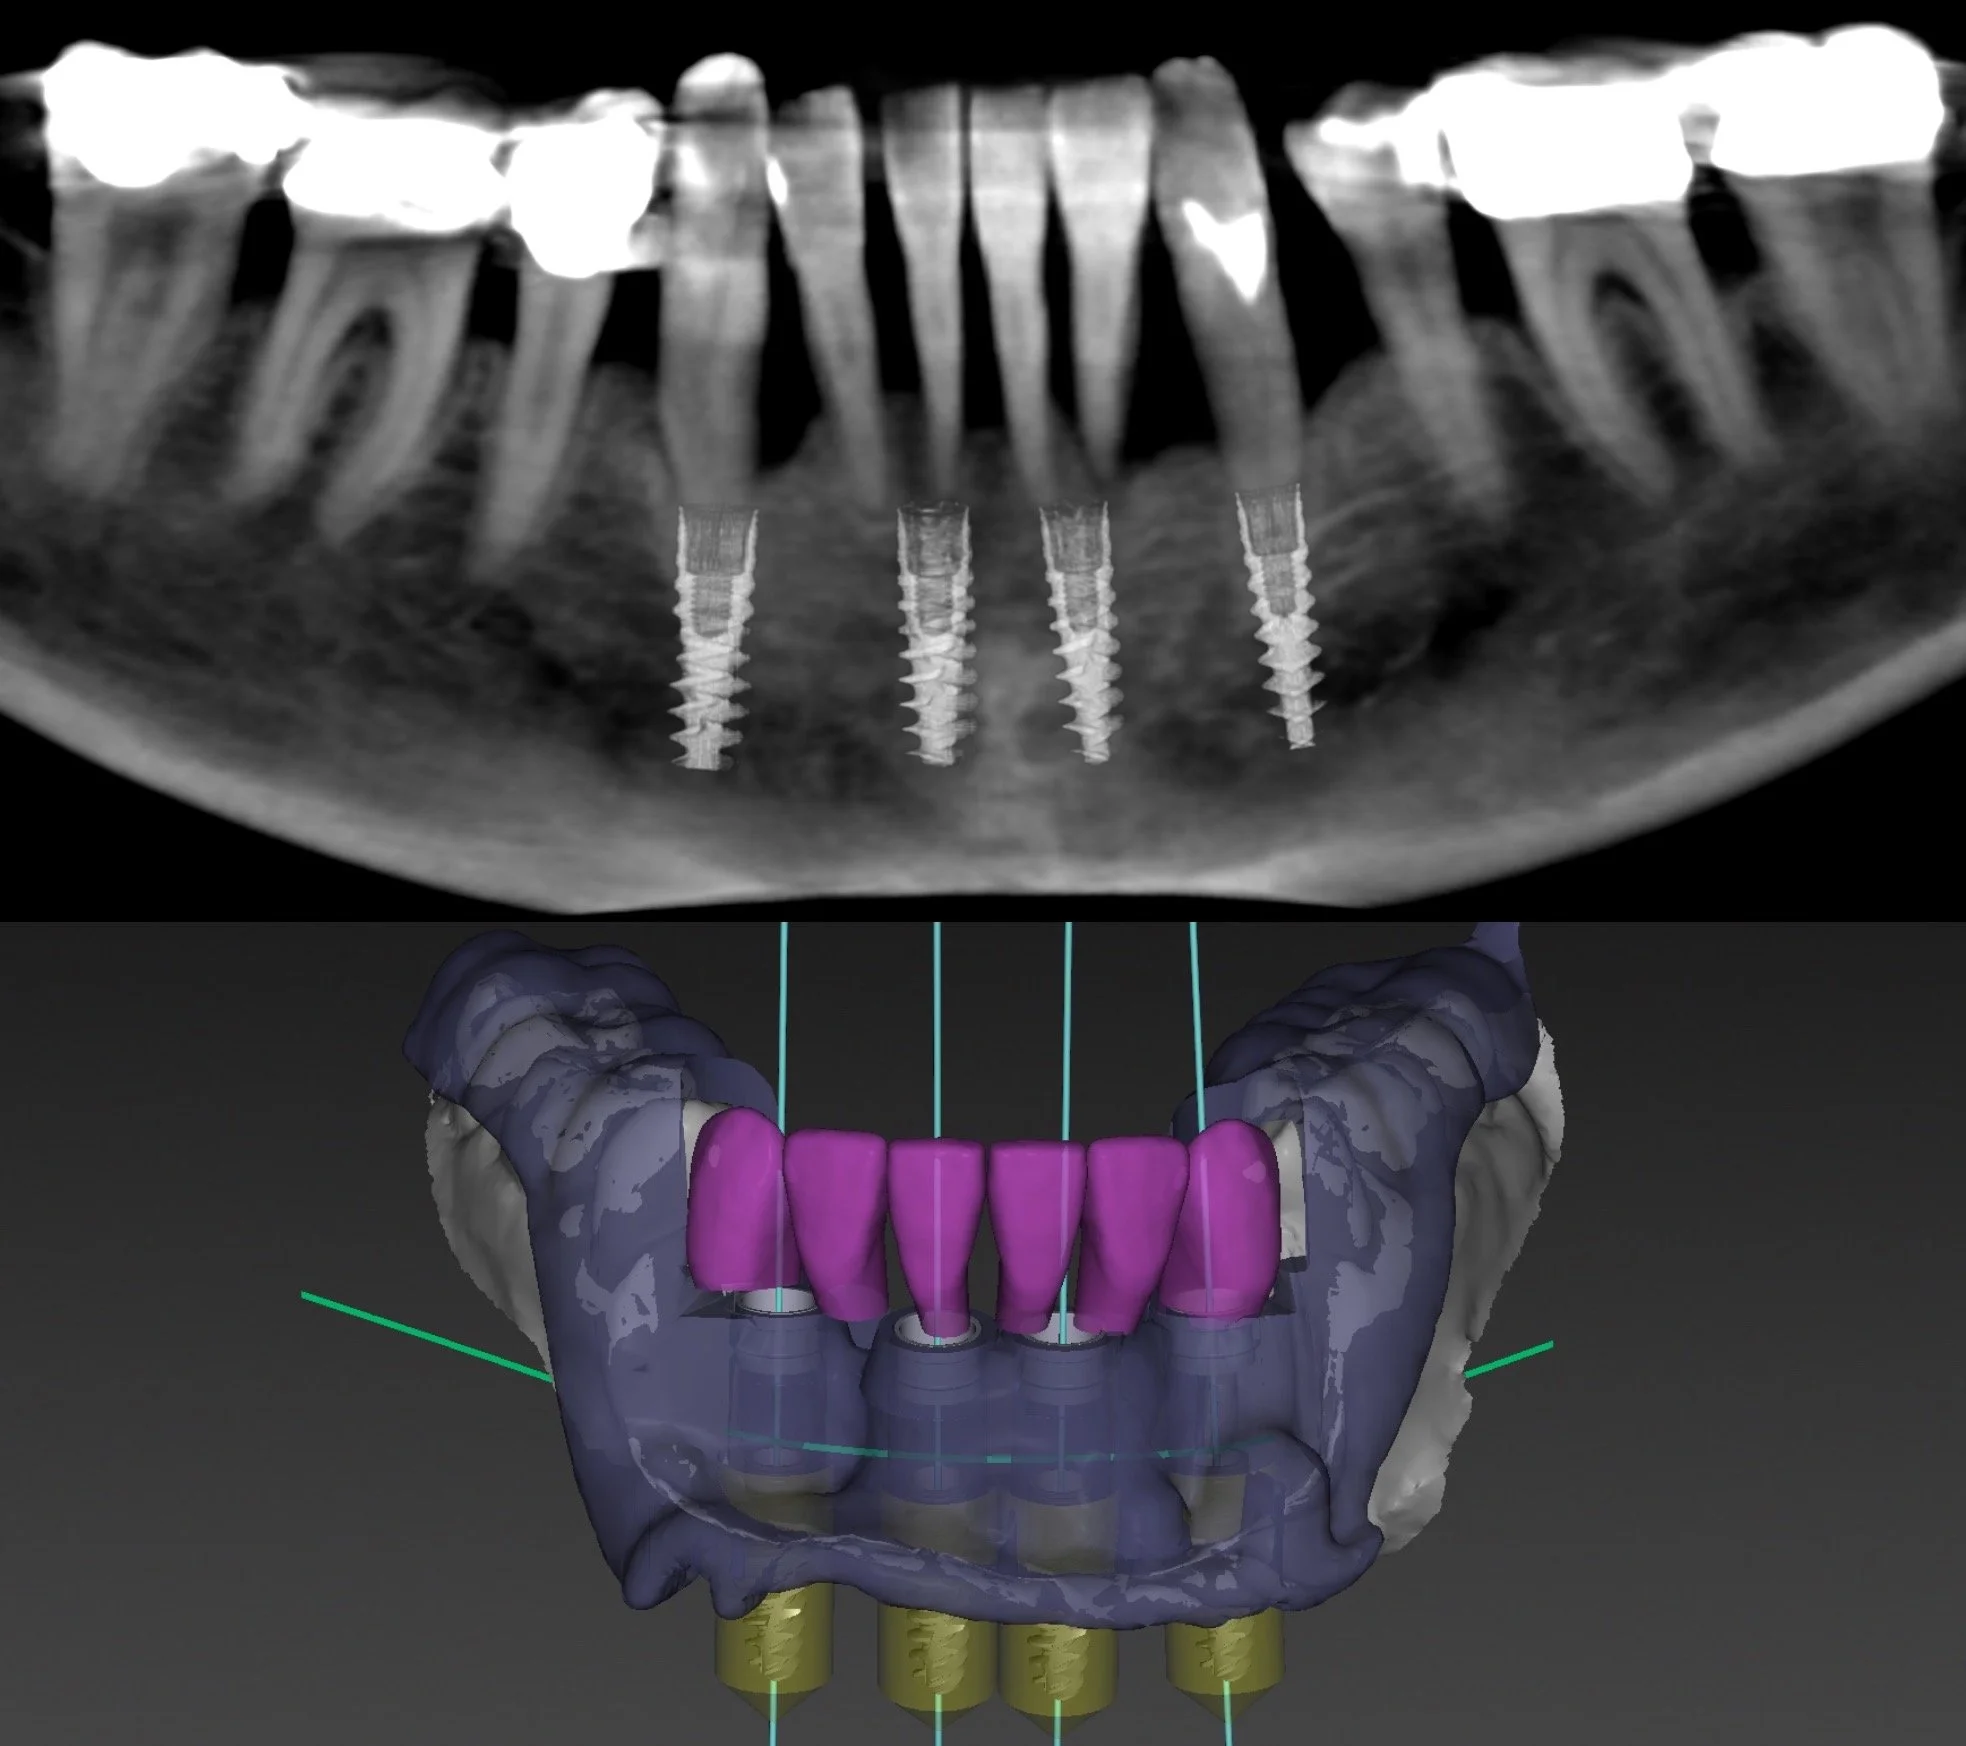

4 IMPLANTS + ZIRCONIA PROSTHETIC

Porcelain, Titanium, Allograft, and Xenograft.

Dr. Heldt, 2021. Newport Beach, California.

IMPLANT: 6 extractions, allograft, xenograft, alveoloplasty, 4 immediate implants (NobelActive) placed with a Fully-Guided surgical stent, immediate 3D printed temporary teeth.

COSMETIC: Zirconia Framework in Shade A1. Diagnostic wax-up with patient-approved temporaries for shape and shade. Light translucency and staining. Pink porcelain in Shades G2 - G5. Surgical + Restorative by Dr. Heldt.